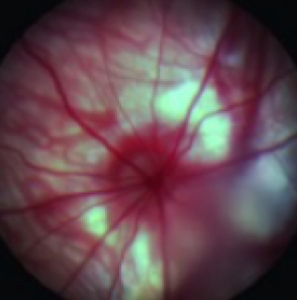

Ocular Assessments

CBI provides special techniques including, OCT (See our OCT video), ERG, ocular ultrasound, gonioscopy, tonometry, laser photocoagulation, slit lamp, funduscopy, pachymetry, Schirmer test, phenol red thread test, hypoxic or hyperoxic chambers, retinal angiography, device implantation, lens removal or insertion, whole mount preparation, ocular histology and immunohistochemistry and ocular photography.

- Funduscopy and Angiography

Histology Images